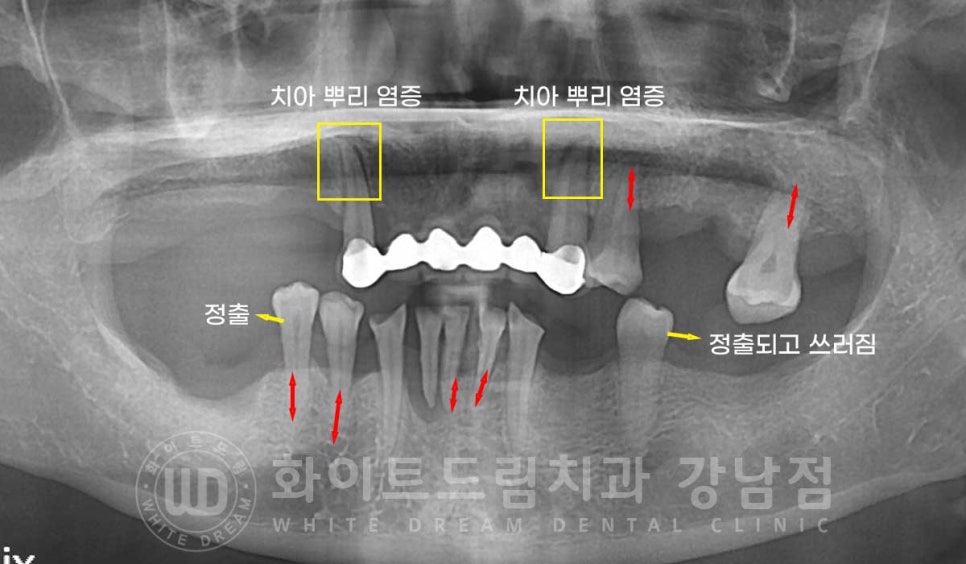

▲ 치주염 전체임플란트 치료 사례

오늘은 이 치주염으로 전체 임플란트 치료를 진행하신 40대 여성분의 치료 사례를

알아보려 하는데요.

40대 밖에 되지 않으셨으나 심각한 치주염으로 치아가 심하게 흔들리고

대다수의 치아가 상실되신 분입니다.

상악 전치부 브릿지와 남은 하악 치아들로 식사를 하셨던 분이신데

어금니가 없어 앞니로 식사를 하시는 분들은

대부분 앞니가 이렇게 심하게 마모되고 치아의 상태가 좋지 못한 경우가 많습니다.

어금니가 버티는 하중에 비해 앞니가 버틸 수 있는 하중이 적기 때문인데요.

어금니는 음식을 잘게 다지는 역할을 하기에 앞니에 비해 4-5배가량의 하중을 버틸 수 있답니다.

하지만 앞니는 뿌리도 짧고 크기도 작기 때문에 이렇게 어금니의 역할을 대신하게 되면

굉장히 빠른 속도로 손상되기 시작합니다.

환자분은 현재 남아있는 치아들이 심하게 흔들리는 상태였습니다.

치주염으로 잇몸뼈가 많이 녹아내려 잇몸뼈가 치아를 잡아주는 면적이 크게 줄었기 때문입니다.

치아 하나씩 동요도 검사를 진행하여 발치 여부를 확인했고

남아있는 치아 들 중, 하악 43, 33번 치아를 제외하고 남은 치아는 발치 & 보철은 모두 제거하기로

결정되었습니다.